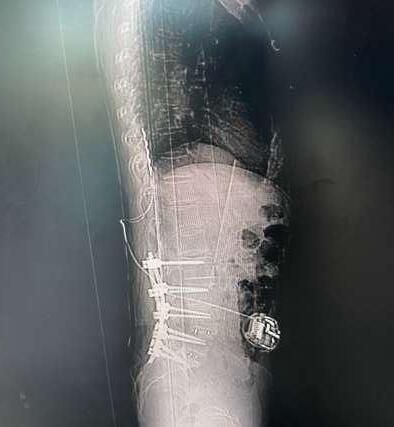

En enero de 2025, el equipo de columna de Clínica Bupa Santiago realizó una cirugía para el tratamiento de dolor crónico intratable, mediante la implantación de un estimulador medular de última generación. El procedimiento fue liderado por el Dr. Miguel Naranjo, traumatólogo especialista en columna, y marca un hito en el abordaje del dolor lumbar persistente, especialmente en pacientes que han agotado otras alternativas terapéuticas.

La paciente, con antecedentes de dolor lumbar crónico, había sido intervenida hace nueve años con una fijación y artrodesis de columna, sin lograr una resolución completa del dolor pese a múltiples tratamientos. Frente a este escenario, y tras una cuidadosa evaluación, se optó por implantar un estimulador medular como última alternativa terapéutica.

Tecnología avanzada al servicio de la calidad de vida

La cirugía consistió en la instalación de una placa de electrodos sobre la médula espinal, conectada a un generador que se ubicó en la zona abdominal. Este dispositivo emite impulsos eléctricos que bloquean la sensación de dolor antes de que llegue al cerebro, permitiendo una mejora significativa en la calidad de vida del paciente.

«El uso de esta tecnología ha demostrado una tasa de éxito cercana al 95%, siempre que exista una correcta selección de candidatos», explicó el Dr. Naranjo. «Hoy, gracias al trabajo de un equipo multidisciplinario y a los avances en diagnóstico, podemos ofrecer esta opción a pacientes que antes simplemente no tenían solución».